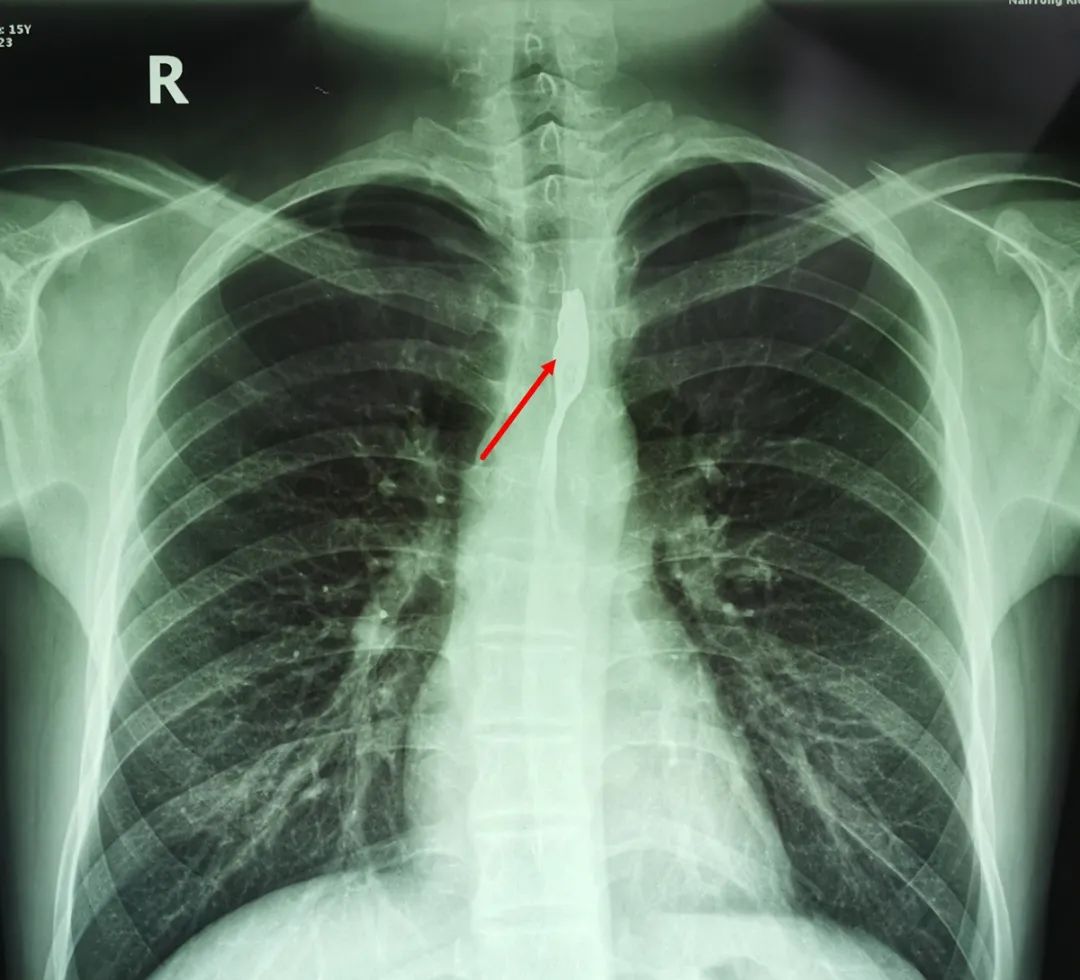

△圖為:我院所取食管異物部分實(shí)例